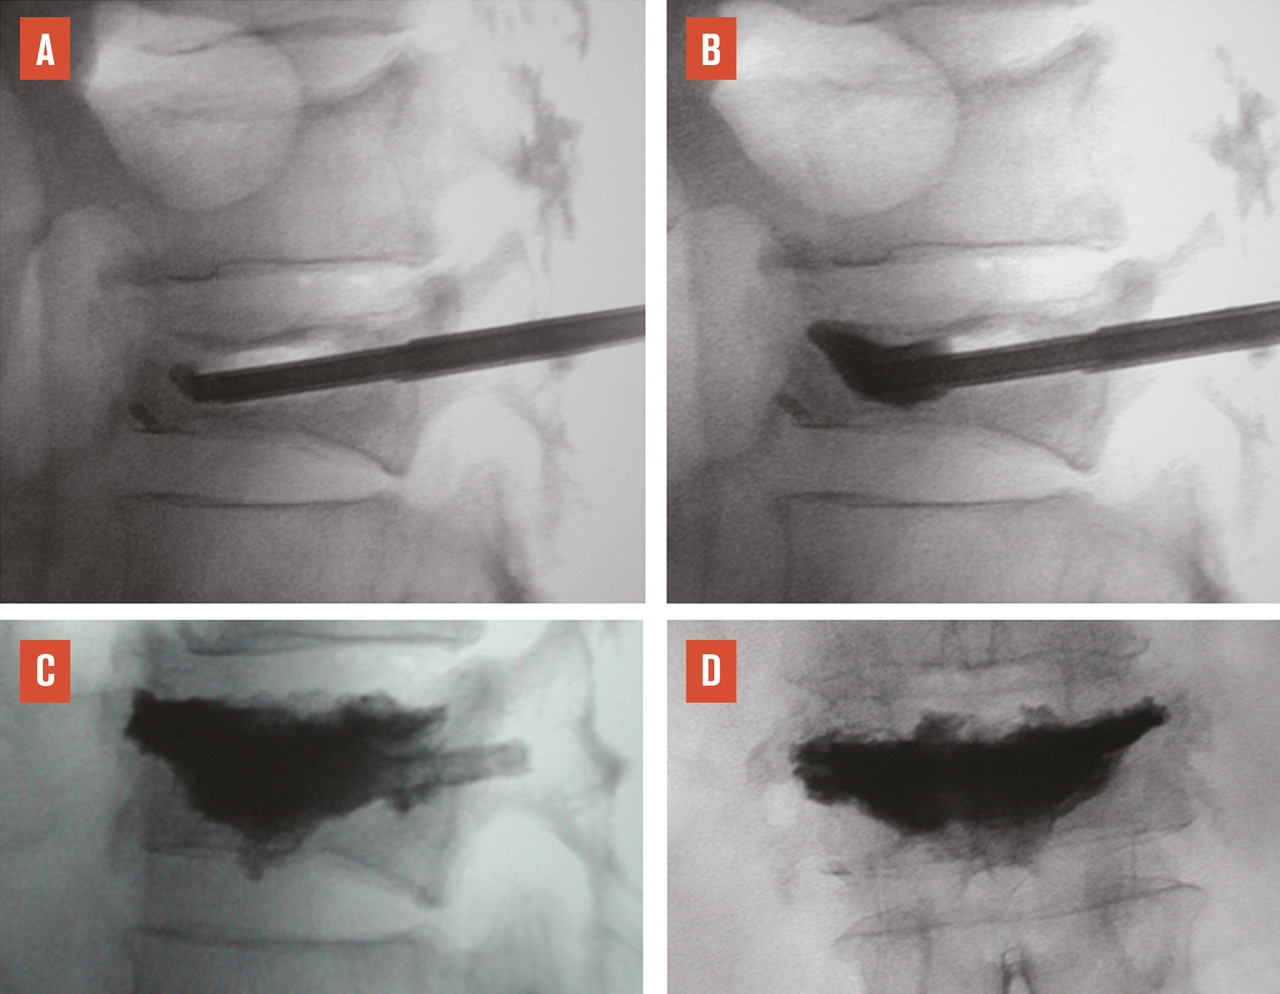

L’objectif d’une cimentoplastie ­percutanée (vertébroplastie et kyphoplastie à ballonnets) est double : antalgie et lutte contre la cyphose et le déséquilibre rachidiens. La vertébroplastie percutanée (fig. 5) consiste à injecter par voie transpédiculaire, dans le corps vertébral fracturé, un ciment acrylique (polyméthylmétacrylate) qui est de même nature que celui que l’on utilise pour sceller les prothèses ­articulaires, et dont la tolérance ­biologique est bien établie. Dans la cyphoplastie (ou kyphoplastie) à ­ballonnets (fig. 7), l’injection est précédée d’une tentative de réexpansion du corps vertébral fracturé, grâce à des ballonnets gonflables afin de regagner une partie de la hauteur perdue et de réduire la cyphose.

L’objectif premier de ces deux techniques est antalgique. Consolider le corps vertébral et soulager les patients invalidés par des douleurs, intenses et persistantes, permet leur remise en charge et la prévention des complications du décubitus. Dans les cas favorables, la consolidation de la fracture et la diminution des douleurs permettent au patient de retrouver une mobilité. La consolidation de la fracture joue un rôle particulièrement important dans les fractures pseudarthrosées avec « vide intrasomatique » (fig. 5). La ­vertébroplastie et la kyphoplastie permettent aussi d’éviter que la fracture progresse (fracture en deux temps) et que l’angle de cyphose ­augmente, ce qui est fréquent. Elles réduiraient aussi la surmortalité associée aux fractures vertébrales.23